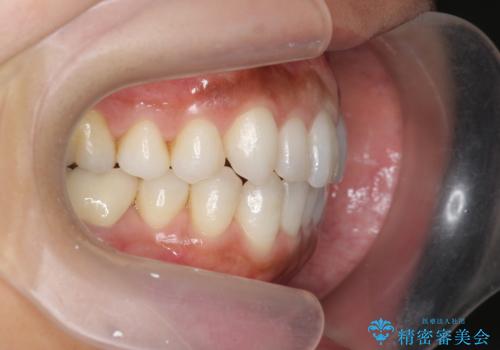

30代女性 前歯のがたつき

- 30代女性

- インビザライン

- 1年5ヶ月

- 前歯のがたつきを主訴に来院。

右下の奥の銀歯も治療しています。

下の前歯を下げるため、IPR(歯をわずかに削る処置)を行っています。